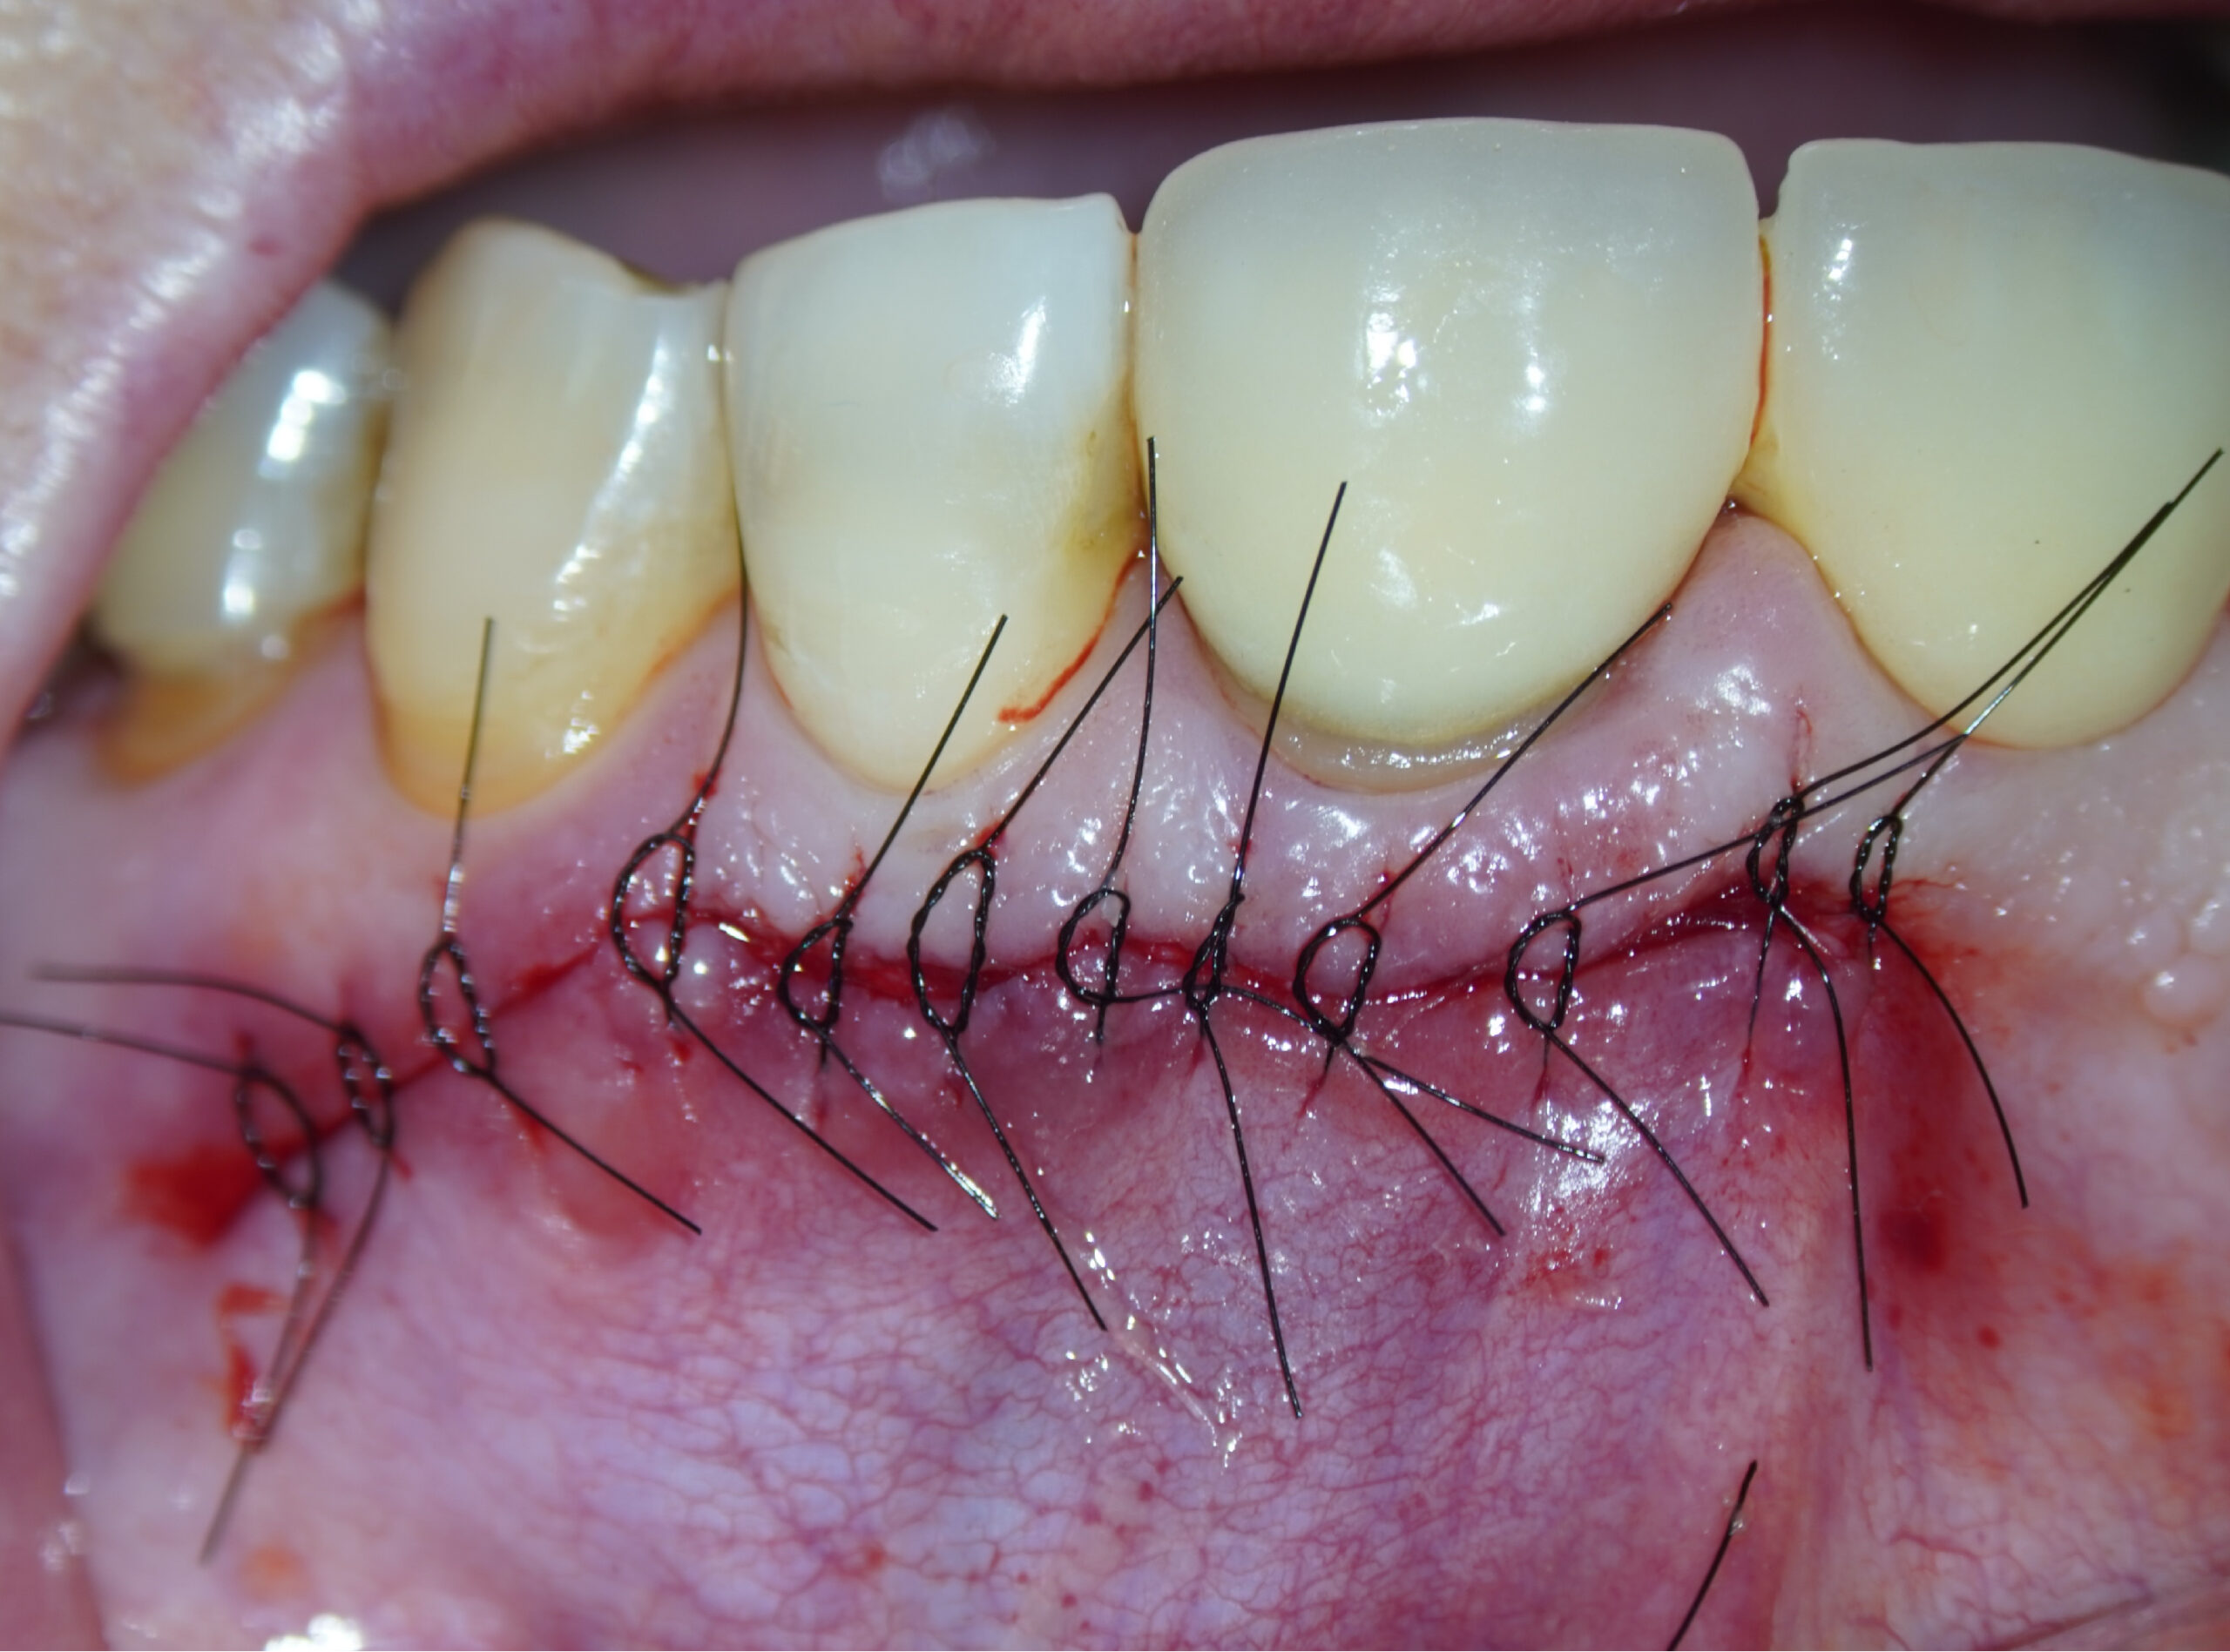

Imágenes del tratamiento

* Haz click sobre las imágenes para verlas a mayor tamaño y a color